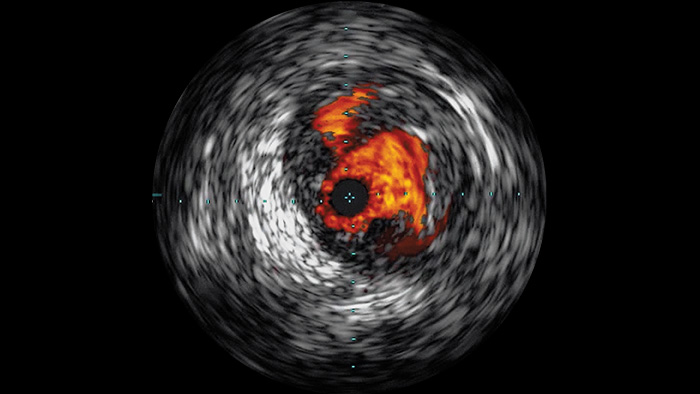

Intravascular ultrasound (IVUS) is a catheter-based imaging technology that allows physicians to visualise blood vessels from the inside out to aid assessment of presence and extent of disease. IVUS helps to decide, guide and confirm the right interventional treatment for each patient.

Visualises high-definition images of vessels with outstanding vascular detail to support precise treatment strategies, navigation and follow-up.